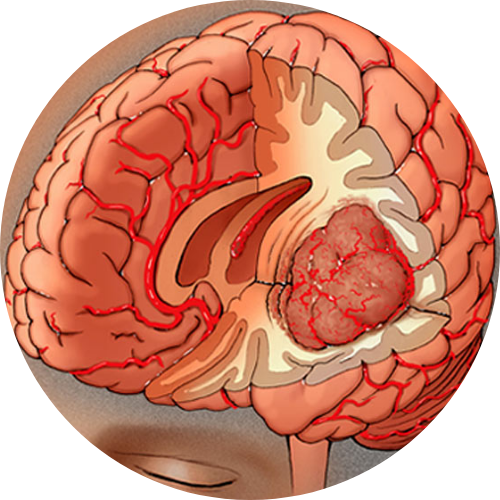

Skull base surgery begins with detailed imaging to understand the tumor’s position and the surrounding nerves and vessels. The surgical approach is planned to reach the area safely with minimum disruption. Depending on the location, surgeons may use endoscopic tools through the nose or small incisions around the head and neck.

Once the tumor is accessed, it is removed carefully while protecting vital structures. Reconstruction may be needed to rebuild the area for proper function and healing. The entire process aims to remove the disease fully while keeping essential functions like vision, facial movement, and swallowing intact.